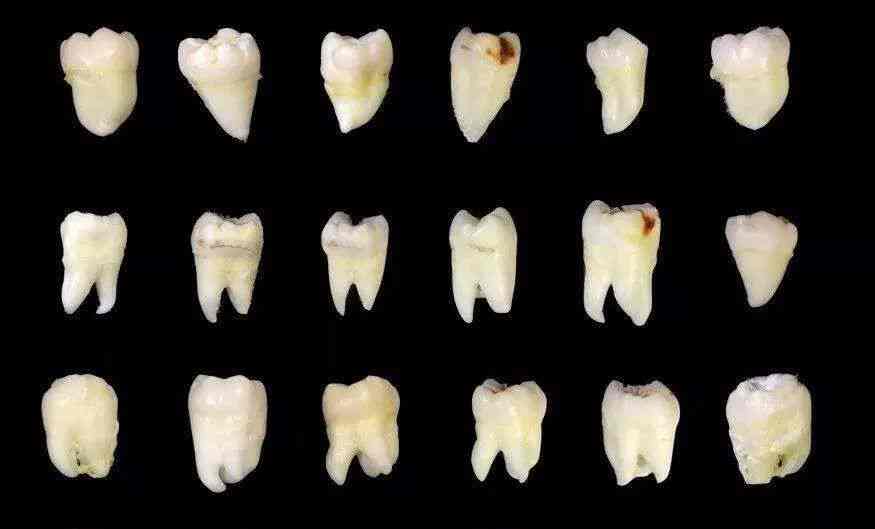

先给大家看一张照片。这些就是在本人这段时间手底下被拔的相对完整的智齿,而更多的智齿其实已经在拔牙过程中四分五裂。即便如此,这些幸存下来的智齿,或多或少也已经出现了各种龋损和破坏。

图源:作者